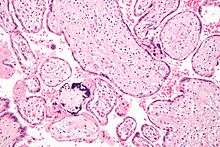

Development

The placenta begins to develop upon implantation of the blastocyst into the maternal endometrium. The outer layer of the blastocyst becomes the trophoblast, which forms the outer layer of the placenta. This outer layer is divided into two further layers: the underlying cytotrophoblast layer and the overlying syncytiotrophoblast layer. The syncytiotrophoblast is a multinucleated continuous cell layer that covers the surface of the placenta. It forms as a result of differentiation and fusion of the underlying cytotrophoblast cells, a process that continues throughout placental development. The syncytiotrophoblast (otherwise known as syncytium), thereby contributes to the barrier function of the placenta.

The placenta grows throughout pregnancy. Development of the maternal blood supply to the placenta is complete by the end of the first trimester of pregnancy (approximately 12–13 weeks).